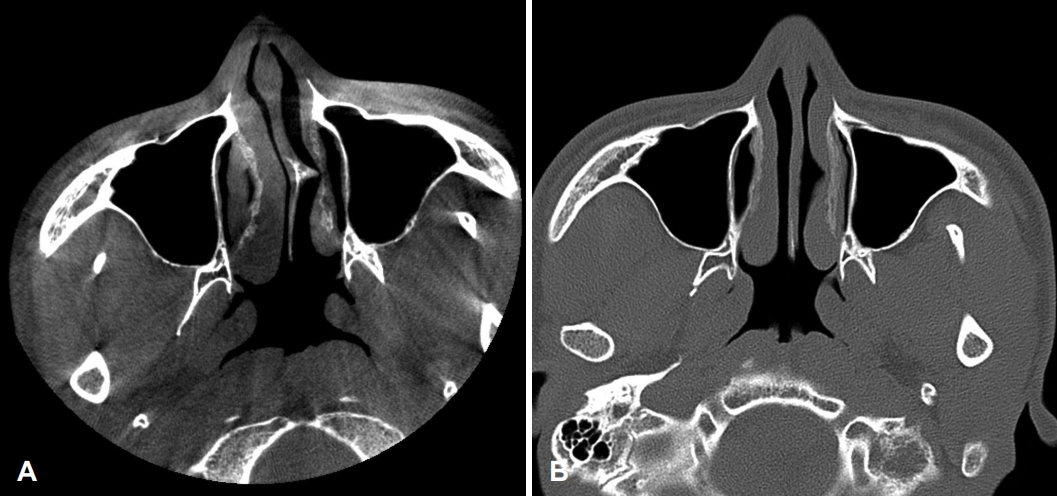

특이 병력이 없는 24세 남자 환자가 1년 전부터 발생한 우측 비폐색 및 간헐적인 수양성 비루, 후비루를 주소로 내원하였다. 비내시경 소견상 좌측으로 편향된 비중격 만곡 및 돌출된 비중격 돌기(septal spur)가 관찰되었고 좌측 하비갑개는 돌출된 비중격 돌기로 인해 함몰되어 있었다(Fig. 1). 타원에서 촬영했던 cone beam CT상에서도 좌측으로 편향된 비중격 및 좌측으로 돌출된 비중격 돌기를 확인할 수 있었으며 부비동염은 관찰되지 않았다(Fig. 2A). 피부 단자 검사는 음성 소견으로 확인되었고, 음향 비강 통기도검사상 좌측 비강이 하강하는 W 모양으로 우측에 비해 좁아져 있는 소견이 확인되었다(Fig. 3A). 상기 소견을 종합해보았을 때 좌측으로 편향된 비중격 만곡증 및 우측의 보상성 하비갑개 비대로 인한 비폐색으로 진단하였으며, 이에 대해 비중격 수술을 계획하였다.

해당 약제를 약 1개월 반 사용한 뒤 재평가를 시행하였으나 환자는 여전히 호흡과 연관된 목의 건조감 및 통증을 심하게 호소하였다. CT 검사를 새로 시행한 결과 좌측 비중격 돌기가 제거되어 비중격의 좌측 편향은 호전되어 있었으나 하비갑개의 용적과 위치에는 뚜렷한 차이점이 관찰되지 않았다(Fig. 2B). 음향 비강 통기도검사상 점막 수축 미시행 시 좌측에 하강하는 W 모양의 비밸브 협착이 여전히 확인되었으나 수술 전 콧구멍으로부터 2.8 cm 떨어진 위치에 존재하였던 2nd minimal cross-sectional area (MCA)부터는 수술 전에 비해 비강 내 용적 확장이 이루어진 것이 관찰되었다(Fig. 3B).

그러나 본 증례에서는 하비갑개의 용적 축소가 이루어지지 않았으며, 하비갑개 전단에 위치한 내비밸브의 단면적 변화 또한 없었다. 비강 통기도 검사상 내비밸브를 의미하는 첫 번째 MCA는 수술 전 콧구멍에서 1.56 cm 거리에 위치하였으며 면적은 0.46 cm2였고, 수술 후에 콧구멍으로부터 1.43 cm 거리에 0.43 cm2의 면적으로 측정되어 수술 전과 큰 차이를 보이지 않았다. 두 번째 MCA는 수술 전에는 콧구멍에서 2.77 cm 거리, 면적 0.66 cm2로 측정되었으나 수술 후에는 콧구멍에서 4.32 cm 거리, 면적은 1.24 cm2로 측정되었는데, 수술 전에 비중격의 돌기로 인해 형성되었던 두 번째 MCA가 수술 후 콧구멍으로부터 약 4 cm 거리에 위치하는 일반적인 두번째 MCA인 중비갑개의 전단부위로 바뀌었음을 시사한다. 즉, 본 증례에서 해부학적 구조 변화는 비갑개가 아닌 비중격의 교정에 의해 주로 발생하였음을 알 수 있다.

본 논문의 한계점으로는 수술 전 CT 해상도 저하로 CT measurement를 이용한 해부학적 평가를 시행하지 못하였다는 점이 있다. 추후 이와 관련된 추가적인 보고가 있다면 빈코증후군의 기전을 밝히는 데 도움이 될 것이다.